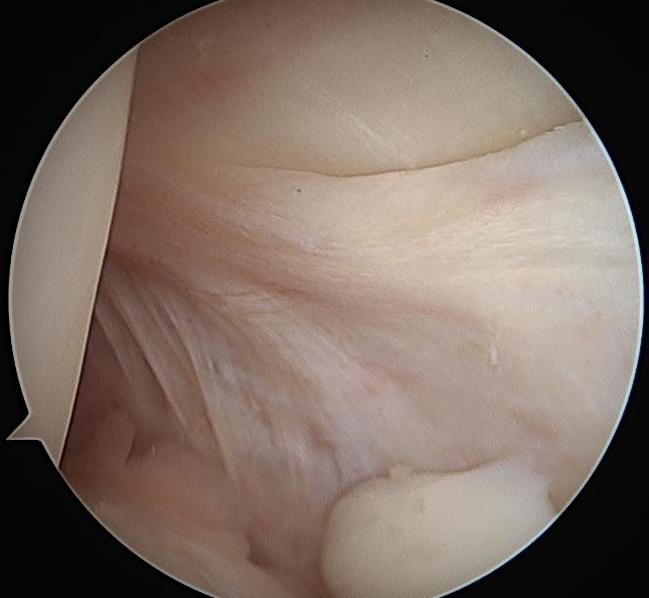

Clear tibial origin

Need adequate visualisation of the PCL facet

- down at least 1 - 2 cm below articular surface

- combination of shaver and electrocautery

- usually need to release some of the capsular insertion onto posterior tibia

PCL facet 1PCL tibial tunnel

PCL tibial facet                                                           Tibial tunnel beath pin